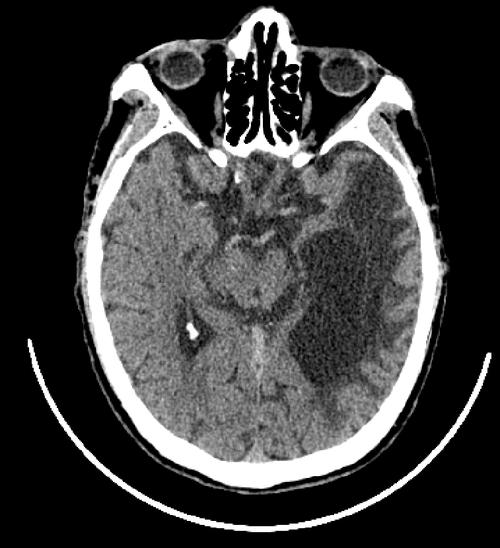

影像学上的表现

- CT扫描:

- 急性期:低密度灶。

- 慢性期(形成软化灶后):边界清晰的低密度灶,其密度与脑脊液相近,由于体积缩小,局部可能会有脑沟、脑池增宽或脑室局部扩大的现象(即脑萎缩)。